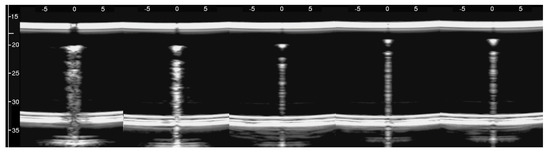

Figure 9 shows four lung US images which have been selected from a data set previously acquired by means of a Toshiba Aplio XV scanner in our Respiratory Department during a study which was approved by the local Ethics Committee CEAVNO (study number 1089 approved on January 30, 2017). The two images on the left were acquired with a PVT-375BT convex probe and a central frequency equal to 6 MHz. The two images on the right were acquired with a PLT-704AT linear probe and a central frequency of 7.2 MHz. From left to right, the first image shows two B-lines; the first B-line does not show any modulation, while the second shows a slightly confused modulation. The second image shows a modulated B-line and the third shows a non-modulated B-line. The last image on the right shows a modulated B-line. An analogy with the experimental results illustrated in Figure 8 emerges, and the physicians’ hypothesis regarding the progression of a lung disorder supports this thesis. According to their hypothesis, the interstitial spaces between the alveoli gradually increase with the progression of a pathology, and the modulated B-lines are related only to the early stages of the pathology.

Figure 9. From left to right, the first image shows two B-lines; the first B-line does not show any modulation, while the second shows a slightly confused modulation. The second image shows a modulated B-line, and the third shows a non-modulated B-line. The last image on the right shows a modulated B-line.